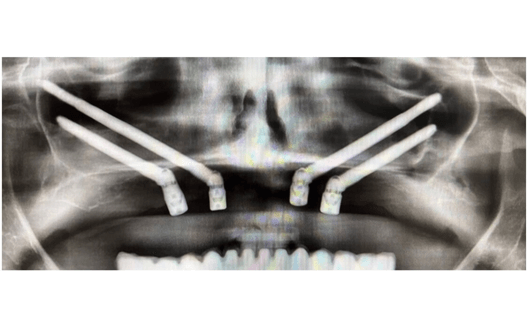

Se planifica rehabilitación completa con 4 implantes Zygoma.

Planificación 3D y confección de férulas quirúrgicas para abordaje guiado.

Se colocan 4 implantes Zygoma según planificación 3D guiada bajo sedación IV, Carga inmediata a las 24 horas.